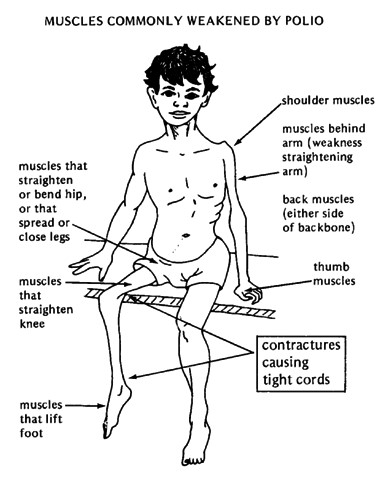

Polio:

Virus, from infected food or water

Virus, from infected food or water- Symptoms: fever, headache, vomiting, stiffness

- Complications: 1% of infected develop muscle weakness in legs, neck, head or diaphragm, meningitis (infection of spinal cord and/or brain)

- Deaths/Statistics: 2-10% of those with paralysis die from suffocation because of diaphragm muscle paralysis, making them unable to breathe.

- Thanks to vaccines, polio cases dropped from 350,000 in 1988 down to on 416 cases in 2013, spreading in the countries of Afghanistan, Nigeria and Pakistan.

- There is no cure for polio, it can only be prevented.

- It mainly affects children under 5 years of age.